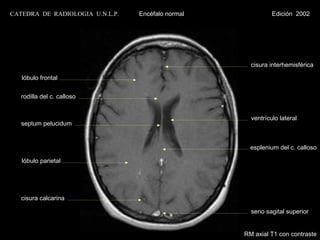

cisura interhemisférica

lóbulo frontal

rodilla del c. calloso

ventrículo lateral

septum pelucidum

esplenium del c. calloso

lóbulo parietal

cisura calcarina

seno sagital superior

RM axial T1 con contraste